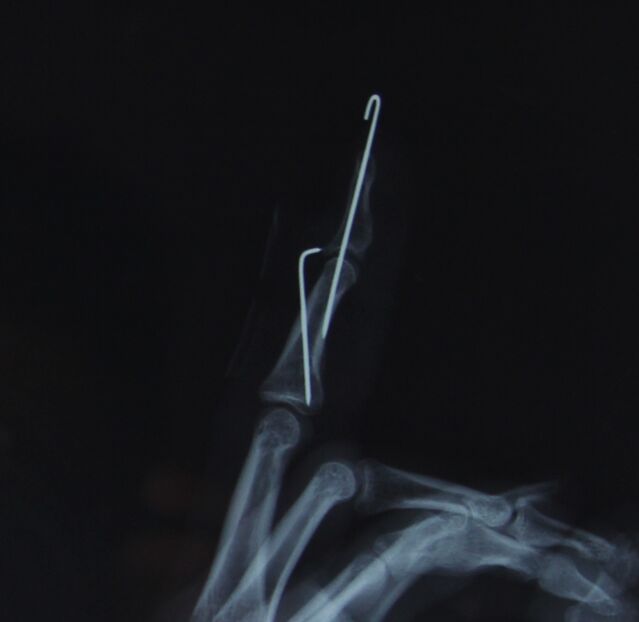

克氏针压扣法治疗骨性锤状指

昨天做了两例

效果都很好